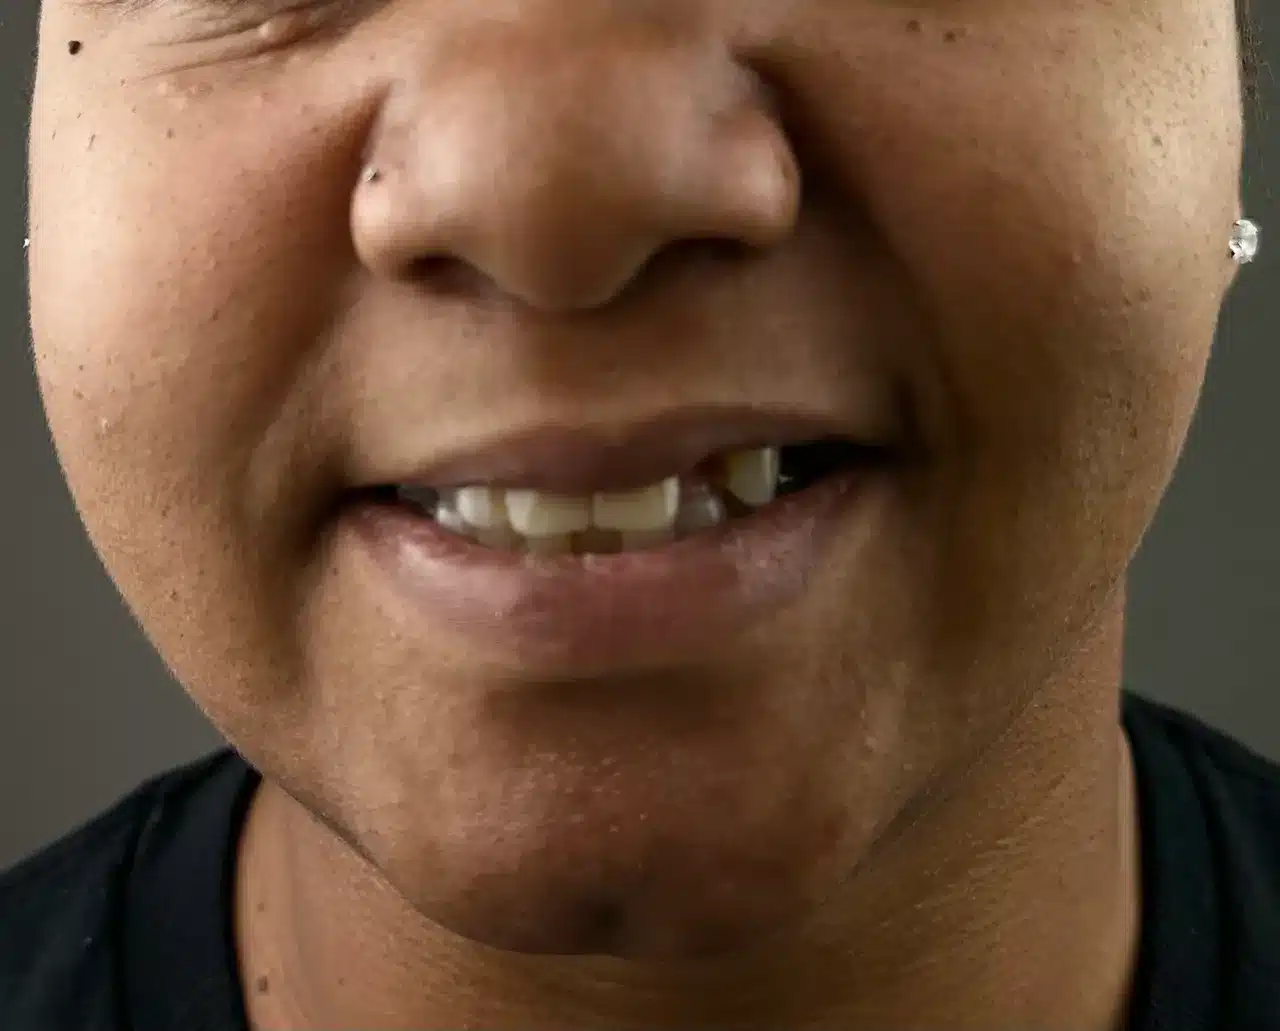

Before